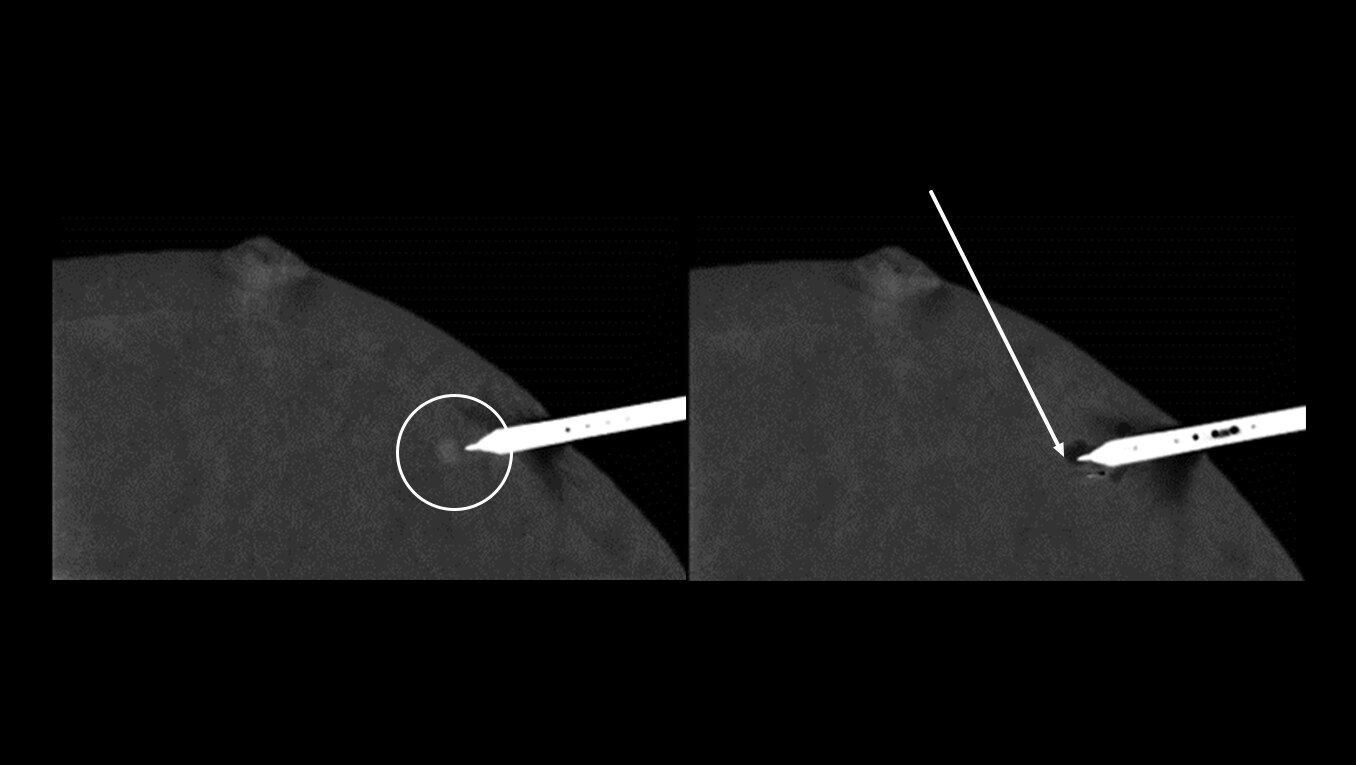

Optimized for accuracy

More confidence in biopsy

Avoid the challenges of seeking correlating lesions in MRI. CEM allows you to see lesions clearly and sample with certainty with the same image guidance.